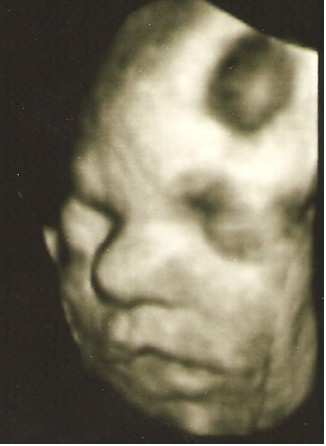

Byłam z Mamą i Mężem i wszyscy troje mieliśmy łezki w oczach jak zobaczyliśmy Młodą na 4D:)

pozdrawiamy :) z uśmiechem Jasi: ---> uśmiech Jasi

Mąż twierdzi, , że Jasia na ostatniej fotce, złości się identycznie jak ja ;)

• Uśmiech Jasi.jpg

Uśmiech Jasi.jpg

21 KB · Wyświetleń: 43